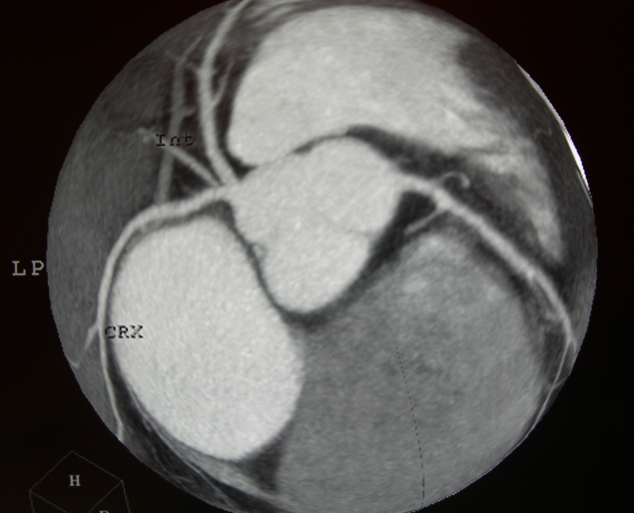

CARDIO IMAGING

immagini significative del cuore e dei grossi vasi

coronaro TC